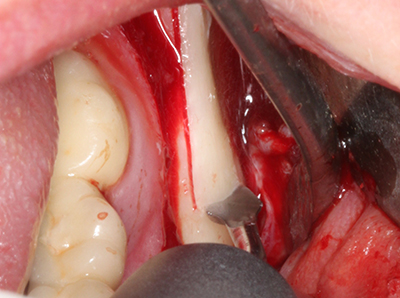

Fig. 18: Preparation of a cortical cover with the piezo bone saw (Piezomed, W&H).

When surgical procedures are performed on bone in the immediate vicinity of sensitive structures such as blood vessels or nerves, rotary instruments pose a significant risk of iatrogenic injury. Piezoelectric devices can be helpful for preparation of bone covers and removal of hard tissue close to nerves, particularly for exposure of nerves after iatrogenic injury but also during nerve lateralization for resective and reconstructive procedures or implant placement (Fig. 17-20). Light contact between the piezotip and the nerve does not generally result in damage but proceeding incautiously with saw-like motions or attachments where a residual bone substrate remains may cause temporary or even permanent nerve damage. However, the risk of damage is considered to be substantially lower than when using saws or milling instruments (Pereira, Gealh et al. 2014).

Another problem with rotary instruments is the possibility of unintentional deflection as a result of tilting or even simply drifting across the preparation surface. Particularly when working close to adjacent teeth and nerves, a piezoelectric attachment can help to improve surgical safety and reduce the risk of injuring neighbouring structures (Pereira, Gealh et al. 2014).